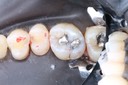

Photos of Clinical Operations

Drs. Peter Kearney, Terry McKay, John St. Germain, and Laurie Vanzella - Mentors